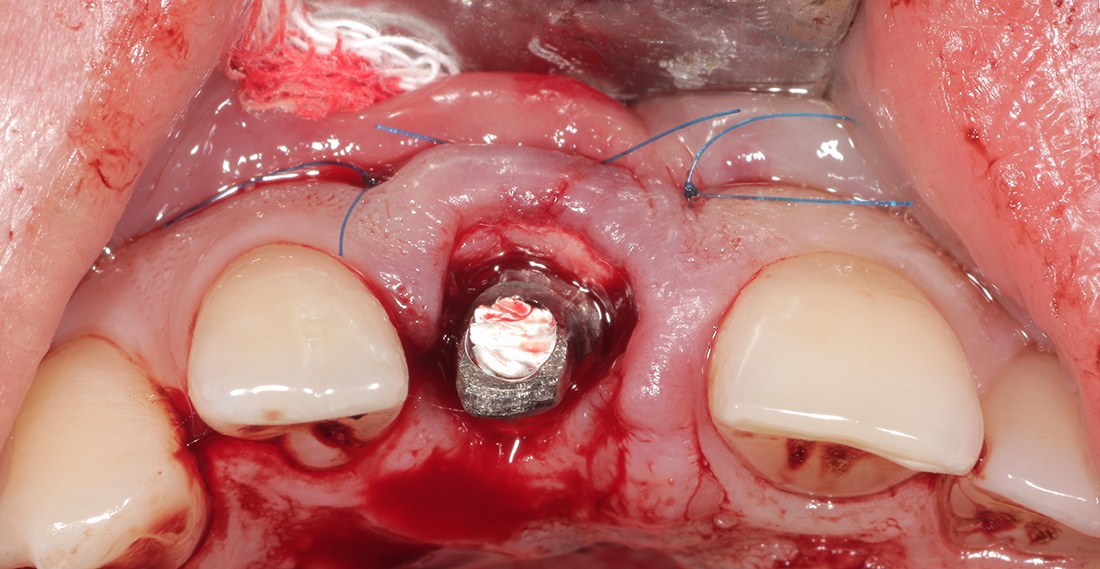

Пациентка П., 26 лет. Обратилась с жалобами на подвижность и боли в области верхнего центрального резца. При клиническом и рентгенографическом обследовании выявлена внутриканальная резорбция корня, поперечный перелом и разрушение наружной костной стенки.

Под местной анестезией был удален зуб, установлен имплант, проведена пластика мягких тканей и фиксирована временная коронка. Через три месяца проведена оценка импланта, и мы перешли к замене временной коронки на постоянную. Опорой для коронки на импланте послужил индивидуальный циркониевый абатмен.